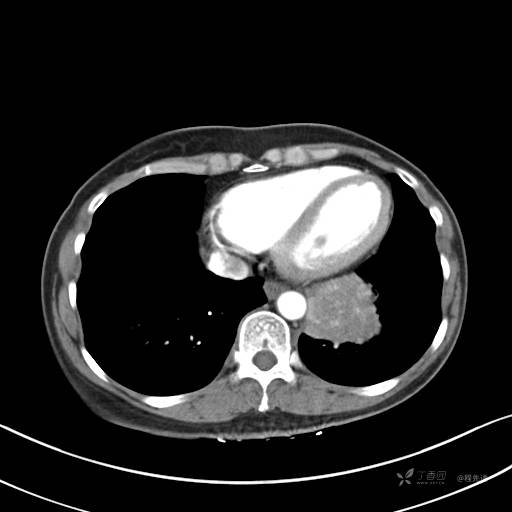

CT平扫

纵隔窗

病灶平扫CT值约31HU